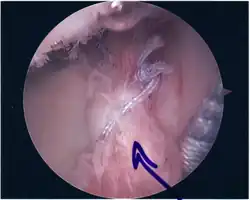

Twelve varieties of SLAP lesion have been described, with initial diagnosis by MRI or arthrography and confirmation by direct arthroscopy.[9]

Surgical treatment of SLAP tears has become more common in recent years. The success rate for repairing isolated SLAP tears is reported between 74-94%.[10] While surgery can be performed as a traditional open procedure, an arthroscopic technique[11] is currently favored being less intrusive with low chance of iatrogenic infection.[12]

Following inspection and determination of the extent of injury, the basic labrum repair is as follows.

- The glenoid and labrum are roughened to increase contact surface area and promote re-growth.

- Locations for the bone anchors are selected based on number and severity of tear. A severe tear involving both SLAP and Bankart lesions may require seven anchors. Simple tears may only require one.

- The glenoid is drilled for the anchor implantation.

- Anchors are inserted in the glenoid.

- The suture component of the implant is tied through the labrum and knotted such that the labrum is in tight contact with the glenoid surface.